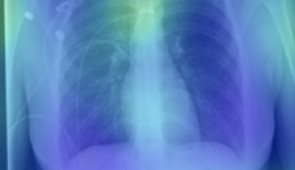

Heat maps

Grad-CAM heat maps of feature importance for positive COVID-19 prediction. Credit: Northwestern University